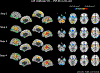

Methods: Thirty-six patients with PSP-RS and 44 age-matched healthy control subjects underwent brain magnetic resonance imaging on a 3-T scanner. The disease epicenter was defined as the peak of atrophy observed in an independent cohort of 13 cases with postmortem confirmation of PSP pathology and used as seed region for SFC analysis. First, we explored SFC rearrangements in patients with PSP-RS, as compared with age-matched control subjects. Subsequently, we tested SFC architecture propagating from the disease epicenter as a determinant of brain atrophy distribution.

Results: The disease epicenter was identified in the left midbrain tegmental region. Compared with age-matched control subjects, patients with PSP-RS showed progressively widespread decreased SFC of the midbrain with striatal and cerebellar regions through direct connections and sensorimotor cortical regions through indirect connections. A correlation was found between average link-step distance from the left midbrain in healthy subjects and brain volumes in patients with PSP-RS (r = 0.38, P < 0.001).